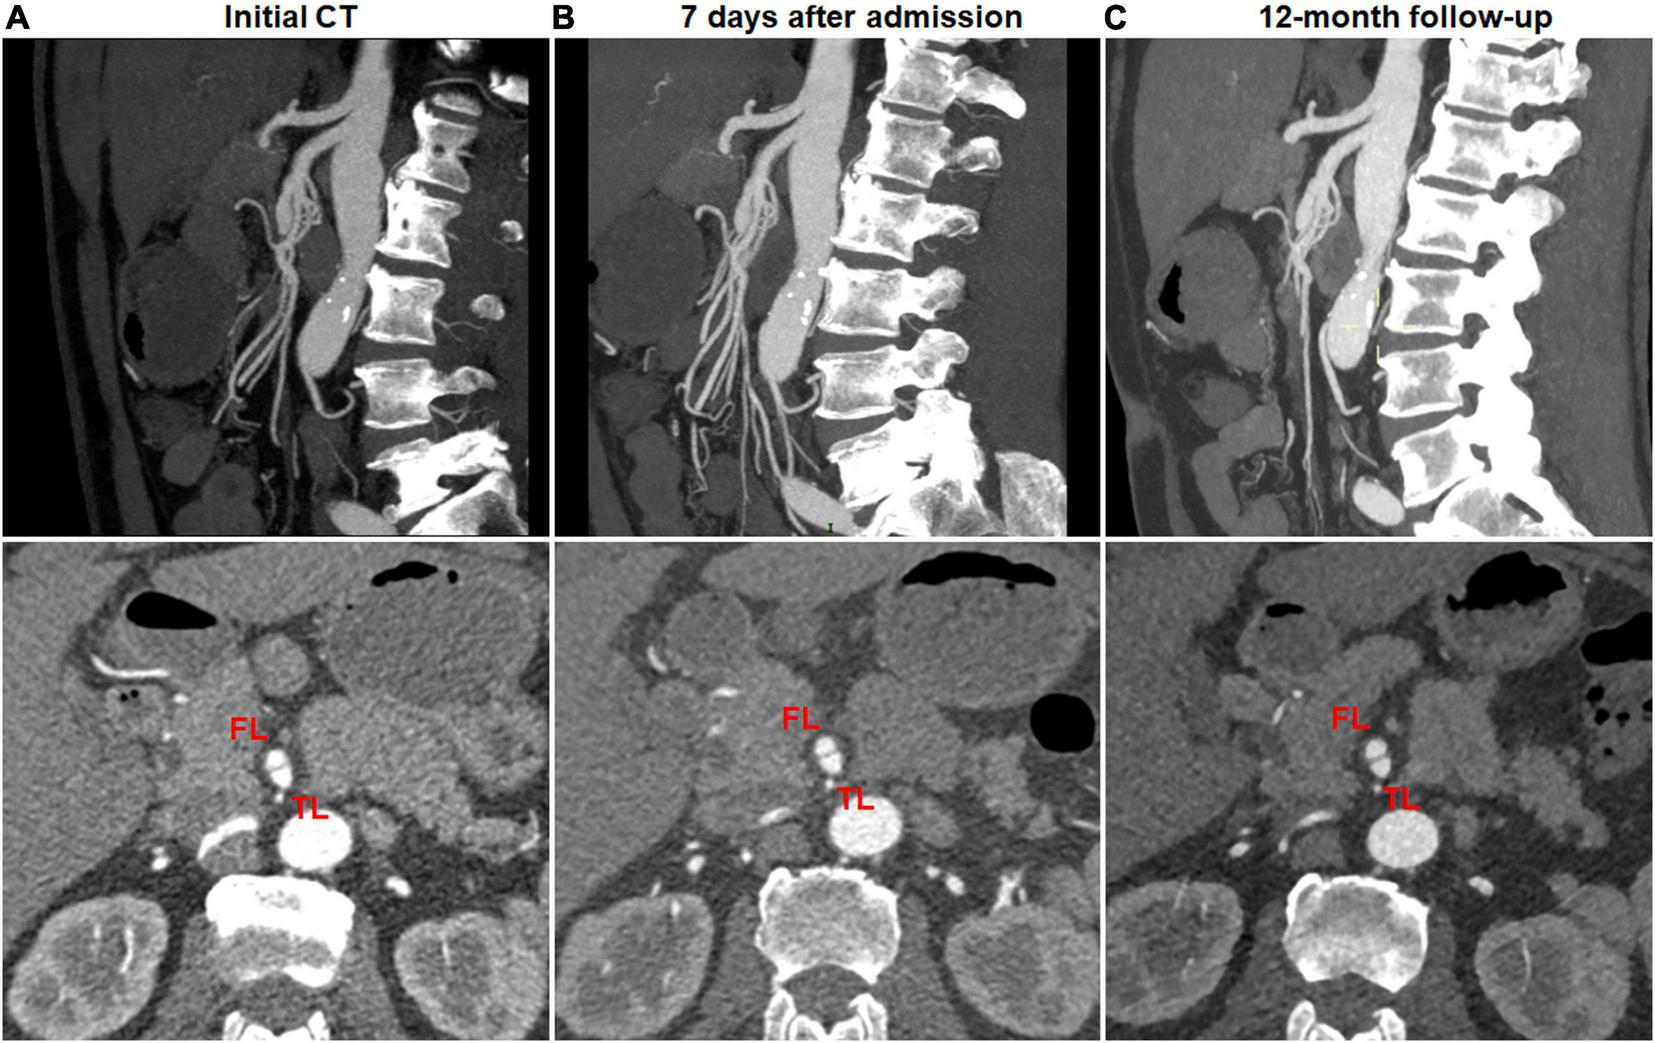

No change on CTA was observed in 13 (92.9%) of 14 type I dissections of patent FL with both entry and re-entry (Figure 5), 9 (27.3%) of 33 type II dissections of “cul-de-sac” shaped FL without re-entry (Figure 6), and 1 (50%) of 2 type V dissections with occlusion of SMA main trunk. In 13 type I lesions, there was no obvious difference on the mean diameter of TL and FL between initial and follow-up CT (3.3 ± 1.5 vs. 3.3 ± 1.2 mm for TL, p = 0.962; 6.0 ± 1.6 vs. 6.1 ± 1.7 mm for FL, p = 0.939). In 9 type II lesions, no difference was observed on the mean diameter of TL and FL between initial and follow-up CT (3.8 ± 1.1 vs. 3.9 ± 1.2 mm for TL, p = 0.930; 7.7 ± 1.3 vs. 7.6 ± 1.2 mm for FL, p = 0.978). Type I lesions showed a tendency for no change on follow-up angiograms.

FIGURE 5

No change of type I spontaneous isolated superior mesenteric artery dissection on follow-up computed tomography (CT) angiography. (A) Initial CT angiography showed patent false lumen and true lumen with both entry and re-entry in a 53-year-old man. (B) One week after conservative management, type I dissection showed no interval change. (C) Nine month later, patent false lumen was sustained with both entry and re-entry as well as no aneurysmal dilatation.